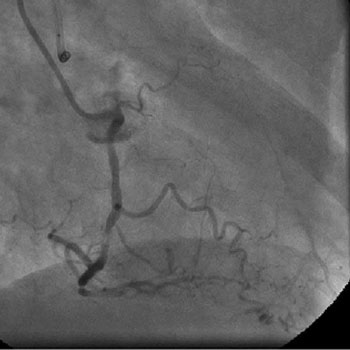

The left system was engaged with XB 3.5 guiding catheter through the femoral route. With the help of a 1.1x1.5mm CTO balloon, we directed a Shinobi guidewire towards the ostial LAD lesion (Figure 4). After making sure that the guidewire was pointing towards the CTO with its tip at the CTO lesion, we used the torquer to gently twirl the guidewire without forcing or overly manipulating it and allowed the guidewire to find its own way through the CTO by patiently twirling it at the lesion site. Within a few minutes, the guidewire jumped through the CTO lesion (Figure 5) and then through the lesion with the help of the CTO balloon (Figure 6). The path was first confirmed by engaging the RCA from the radial approach and injecting dye into the RCA (Figure 7). The CTO was then predilated with a 2.0x30mm Sapphire balloon (Figure 8 and Figure 9) and stented it with a 3.0x36mm DES (Figure 10 and Figure 11). Later the RCA was engaged with a JR 3.5 guiding catheter. A Cougar guidewire crossed the RCA lesion that was directly stented with a 3.0x13mm BMS (Figure 12 and Figure 13).